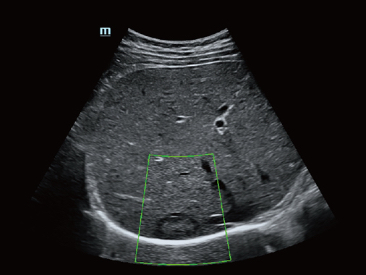

Desde que se fundó la compa?ía, Mindray ha explorado incansablemente nuevas formas de mejorar la confiabilidad del diagnóstico. Con la revolucionaria tecnología de ZONE Sonography?, la nueva plataforma ZST+ de Resona?7 lleva la calidad de la imagen por ecografía a un nivel superior mediante el procesamiento de datos de canal y la adquisición de zona.

Además de la calidad de imagen de primer nivel, Resona?7 también mejora las capacidades de investigación clínica con el revolucionario V?Flow para la evaluación hemodinámica vascular y con la adquisición de planos más inteligente a partir de conjuntos de datos 3D para el diagnóstico del SNC fetal. Al combinar el funcionamiento multitáctil basado en gestos más intuitivo y todas las características clínicas esenciales, Resona?7 realmente lidera las novedades en innovación de ecografías.